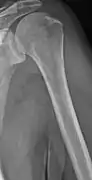

Multiple myeloma in the upper arm

Humerus with multiple myeloma lesions

Same humerus before, with just subtle lesions

The diagnostic examination of a person with suspected multiple myeloma typically includes a skeletal survey. This is a series of X-rays of the skull, axial skeleton, and proximal long bones. Myeloma activity sometimes appears as "lytic lesions" (with local disappearance of normal bone due to resorption). And on the skull X-ray as "punched-out lesions" (raindrop skull). Lesions may also be sclerotic, which is seen as radiodense.[52] Overall, the radiodensity of myeloma is between −30 and 120 Hounsfield units (HU).[53] Magnetic resonance imaging is more sensitive than simple X-rays in the detection of lytic lesions, and may supersede a skeletal survey, especially when vertebral disease is suspected. Occasionally, a CT scan is performed to measure the size of soft-tissue plasmacytomas. Bone scans are typically not of any additional value in the workup of people with myeloma (no new bone formation; lytic lesions not well visualized on bone scan).